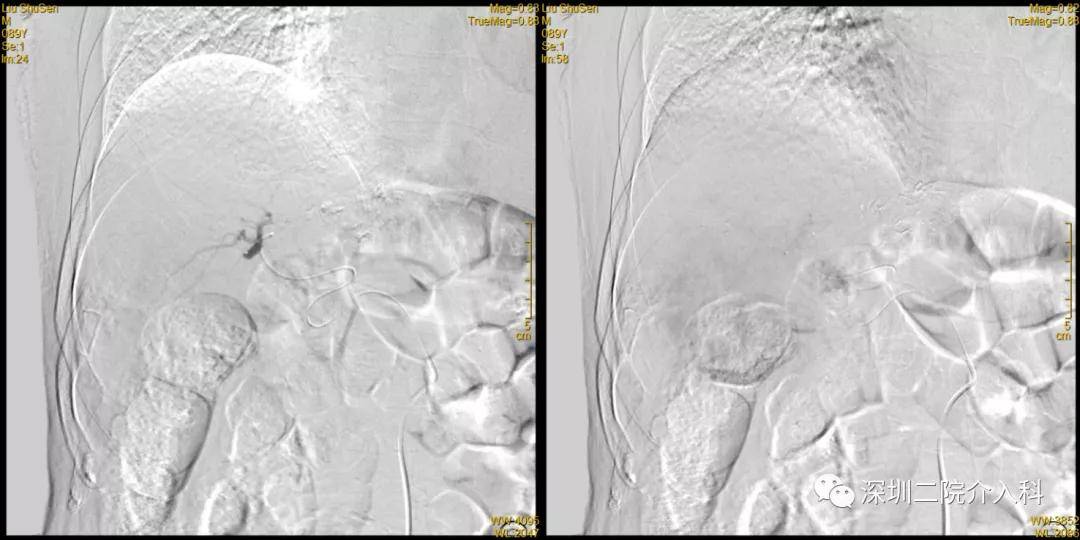

治疗经过:2020-12-18 行TACE术

腹腔干造影

肝固有动脉造影

可见肝右叶明确肿瘤染色